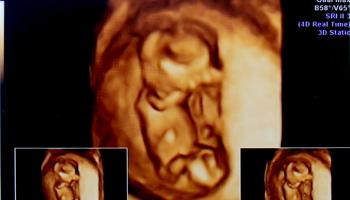

1. 임신 12주 차 - 2.88cm